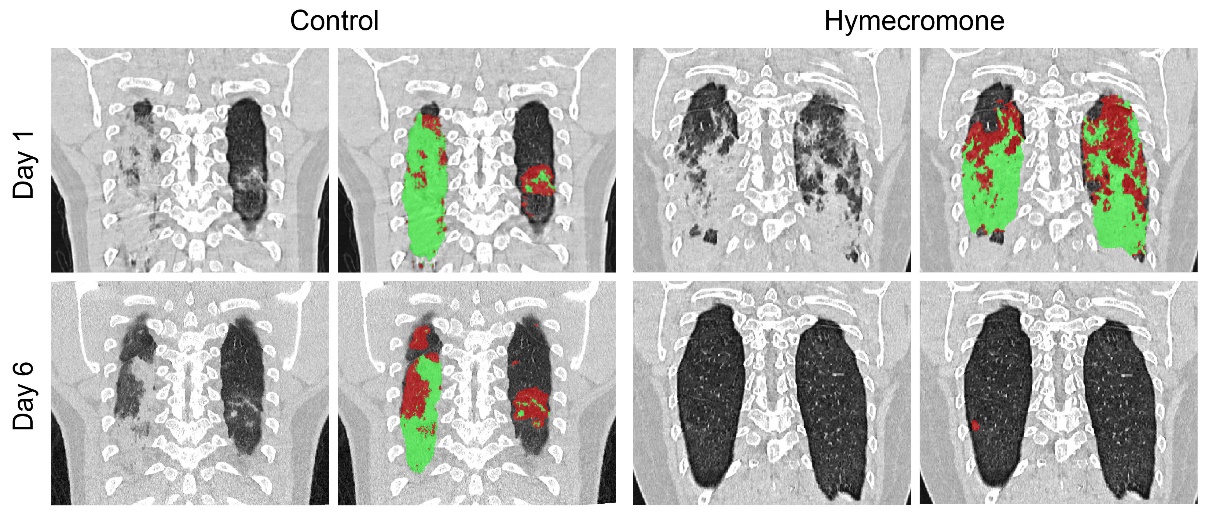

为了进一步评估羟甲香豆素是否可以有效地提升了新冠患者的临床症状,研究团队招募了144名新冠患者。首先,研究者用CT定量分析确定肺部损伤的情况,深入探究羟甲香豆素治疗期间肺部损伤的变化,口服羟甲香豆素的患者中有89%出现肺部病变消退,而对照组中只有42%。如图1,与对照组相比,口服羟甲香豆素后新冠患者肺部病变明显改善。

图1. 羟甲香豆素加快新冠患者肺部病变吸收